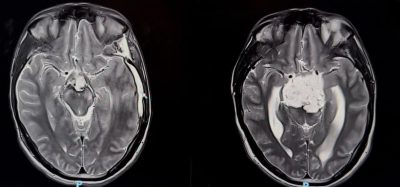

نجح فريق طبي سعودي في مستشفى الملك فهد بجدة عضو تجمع جدة الصحي الثاني بقيادة د. هاني القرشي في استئصال ورم حبلي نادر ومعقد من قاع الجمجمة، خلال ثلاث عمليات جراحية متتالية استغرقت ٣٥ ساعة. الورم كان ضاغطًا على جذع الدماغ والأعصاب القحفية، وتعامل معه الفريق بتقنيات جراحية متقدمة لا تُجرى إلا في مراكز عالمية محدودة، ولله الحمد المريض تعافى وعاد لحياته الطبيعية دون أي عجز عصبي يذكر.